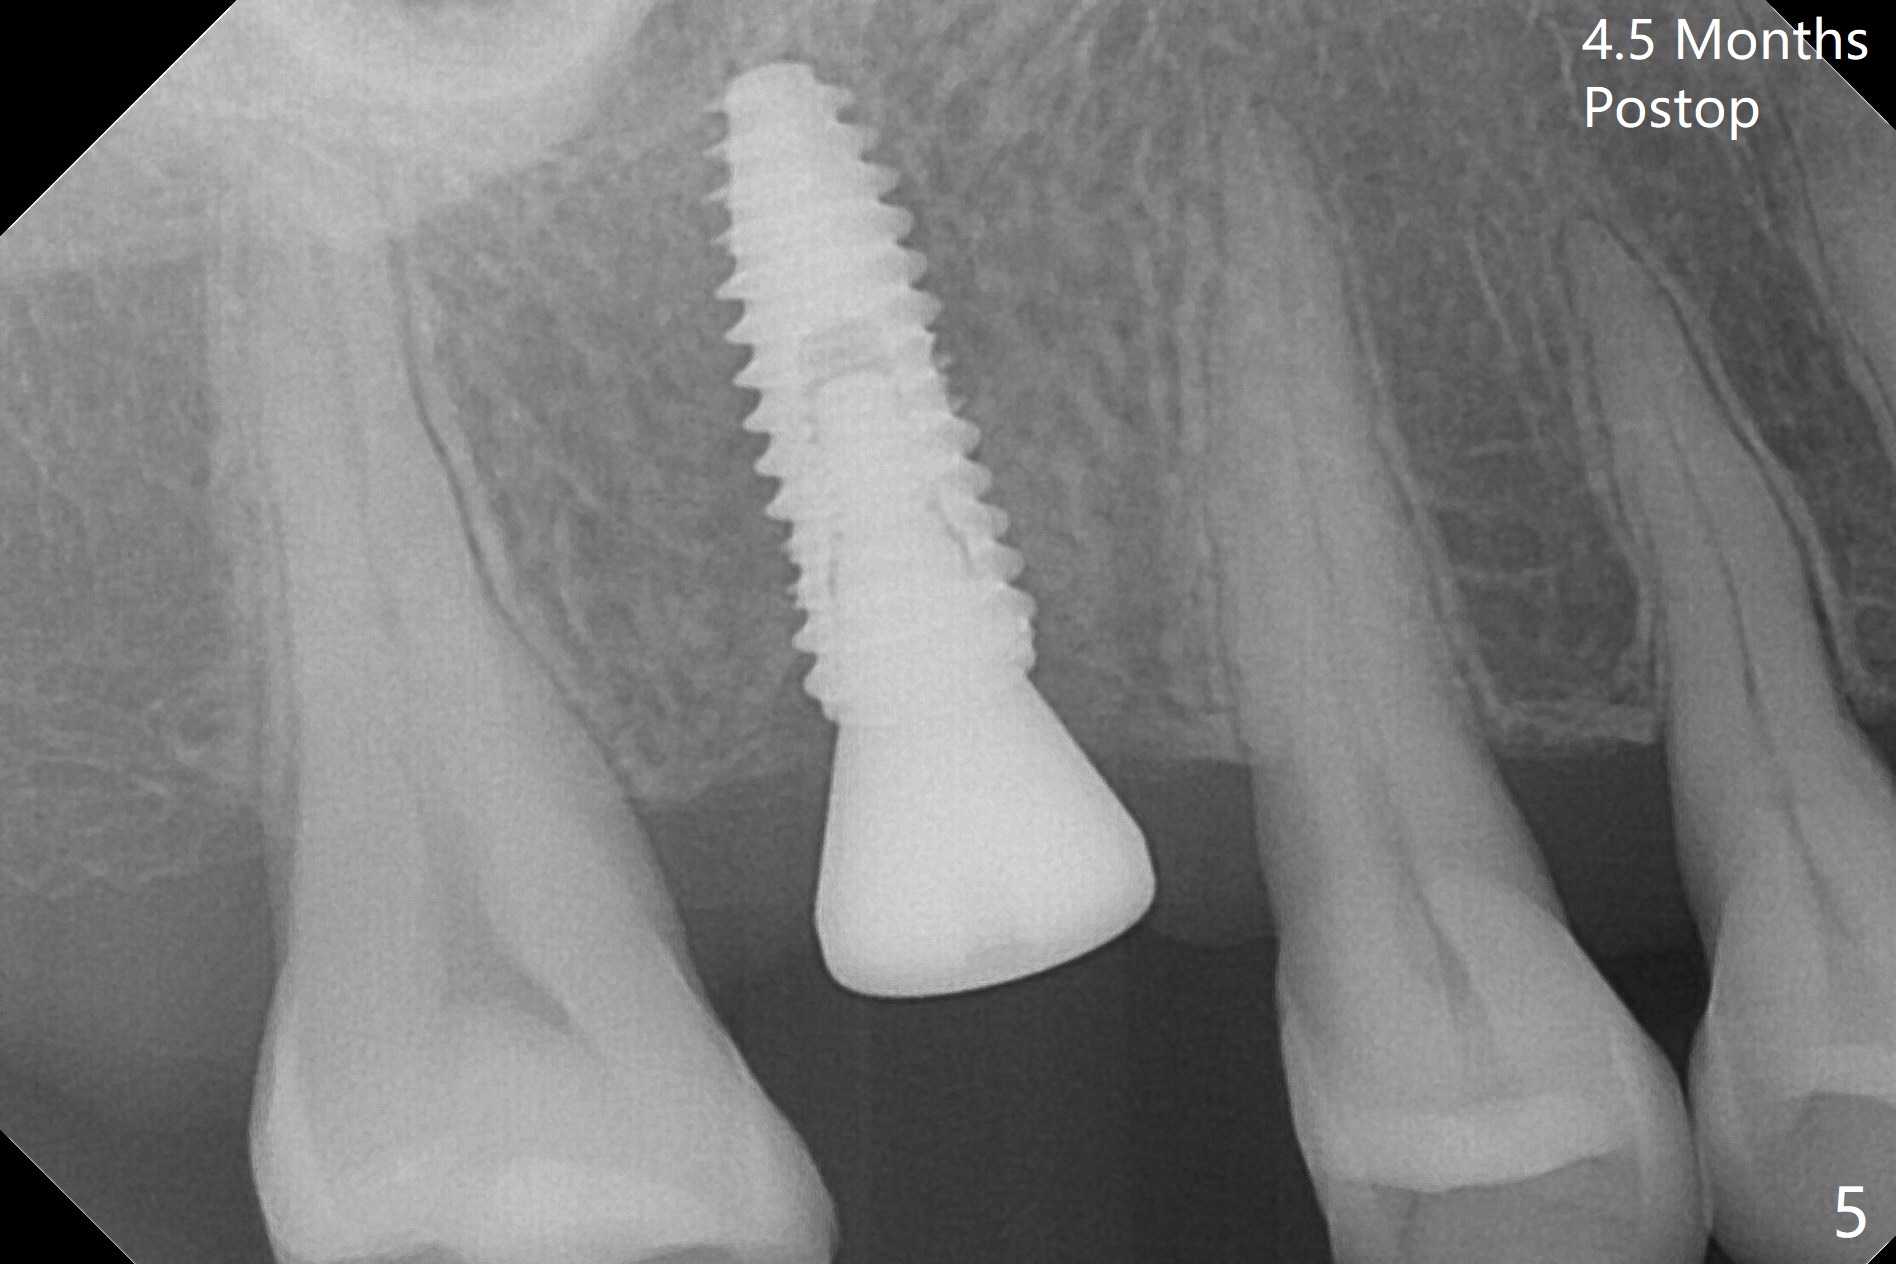

There is mild crestal bone loss 4.5 months postop (Fig.5).  When the patient returns for periodic exam and prophy 6 months post cementation, the crown is found to be loose, which is more likely associated with heavy mastication (long roots) and poor crown/implant ratio.  Since the distal contact is light, the case returns to lab.  PA taken following reseating the repaired abutment/crown shows crestal bone loss, which may be associated with the narrow ridge and/or the loose abutment.  The gingival cuff is less healthy (Fig.6).  The screw becomes loose again 4 months later.  When it is retightened, the distal proximal contact turns open (Fig.7 ^).  The crown appears to turn with the underlying abutment (Fig.8).  After breaking proximal contacts, the crown/abutment is retightened and pick up impression is taken.  It is likely that the abutment was not seated right when abutment-level impression was taken.  The crown table is slightly oversized (Fig.8). Three months later, the screw becomes loose for the 3rd time (unilateral mastication, pain at #19 without RCT).  The abutment hex is not worn.  The crown is removed and the abutment is reseated and torqued 30 Ncm.  Impression is taken for new crown.  The latter is cemented without removing the abutment (Fig.9 (note bone loss)).  In fact the crown/abutment should have been torqued with screw driver buried in place!